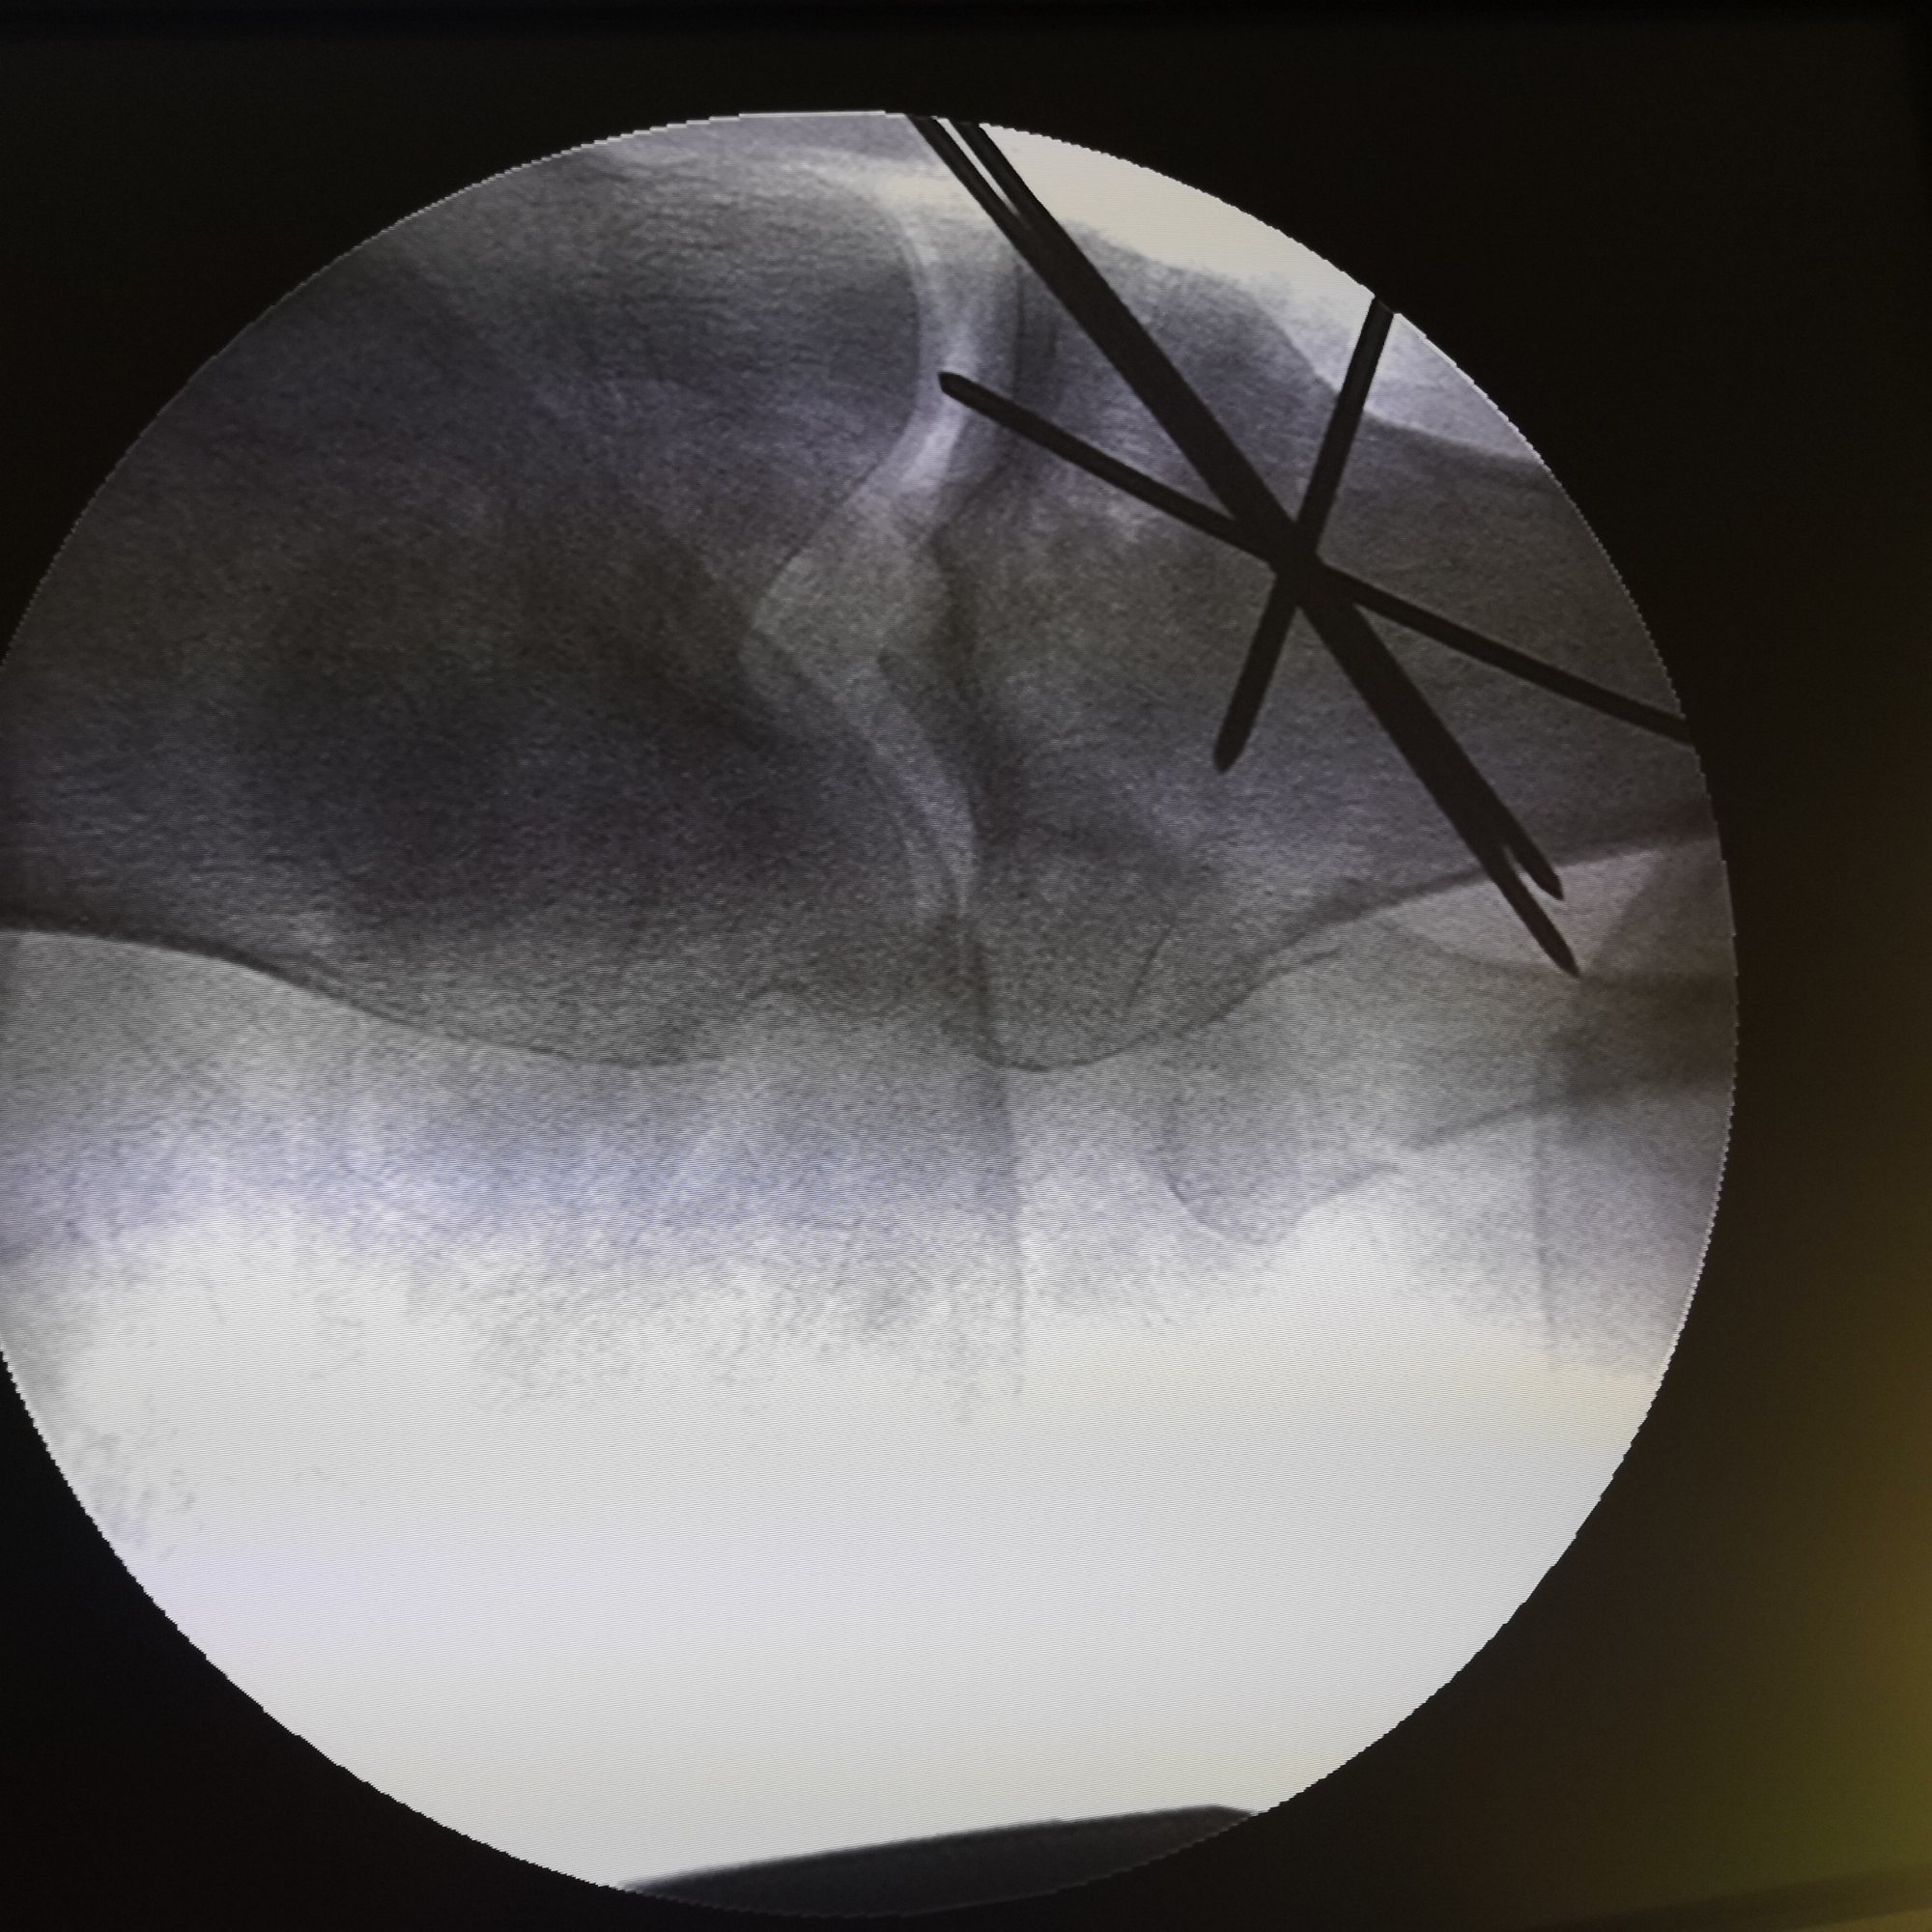

透视复位满意后临时固定。

切开探查

进一步复位、植骨内固定